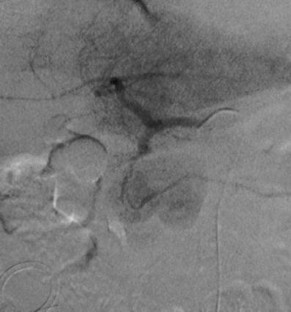

Combined percutaneous thrombin injection and endovascular treatment of gastroduodenal artery pseudoaneurysm (PAGD): case report

A 69-year-old man with a history of acute pancreatitis developed a huge pseudoaneurysm of the gastroduodenal artery (PAGD), as diagnosed by CT scan. The PAGD was treated by percutaneous thrombin injection (2,000 IU) under ultrasound guidance and selective embolization of gastroduodenal artery with microcoils with its complete exclusion. The 6-month follow-up confirmed the complete exclusion of the PAGD sac.

Fig. 3